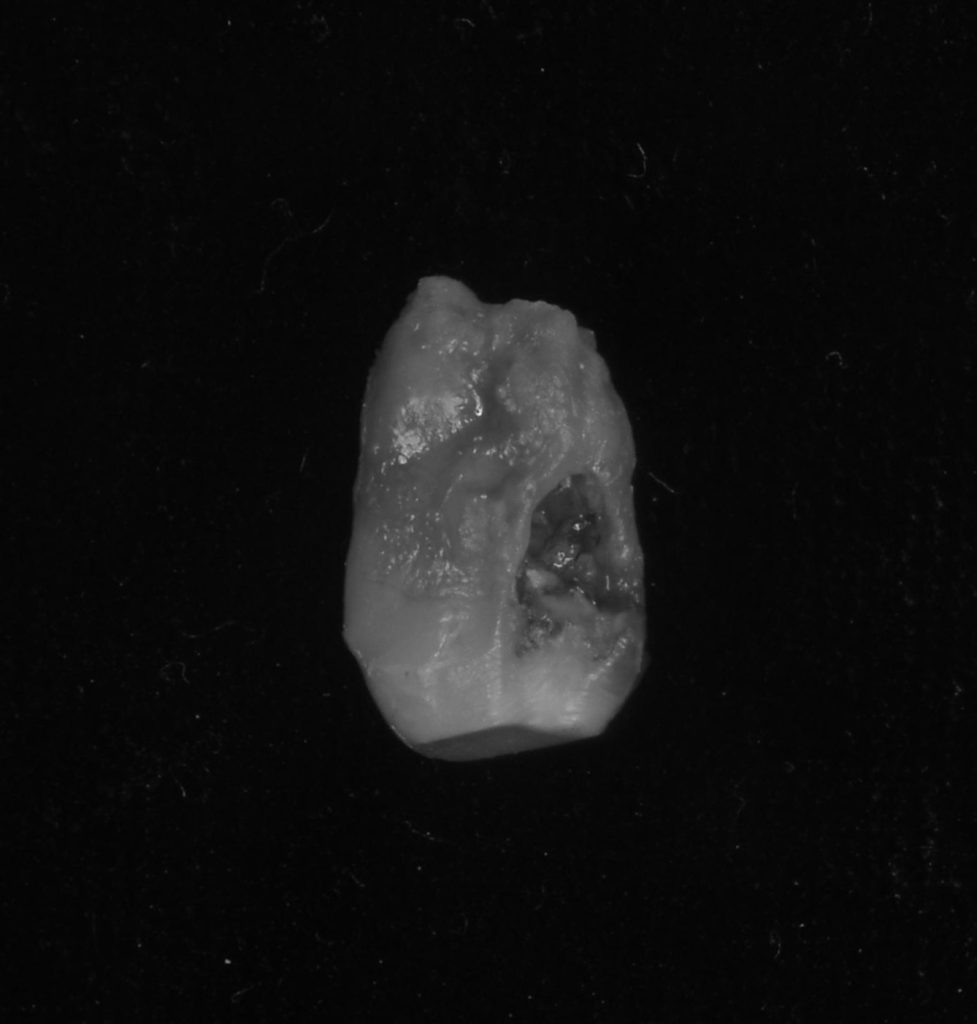

下記の症例は7年前の来院時に外部吸収を起こしていた為、患者さんに抜歯を勧めていました。

その時は、さほど自覚症状もなく、経過観察となりましたが、今回は被せ物が取れ、口臭がするという事で久しぶりに当医院に来院していただきました。

神経がないので痛みというより違和感程度でしたが、抜歯に同意していただき、抜歯と同時にインプラント治療を行い、できるだけ負担を減らし治療期間を短縮する計画を立てました。